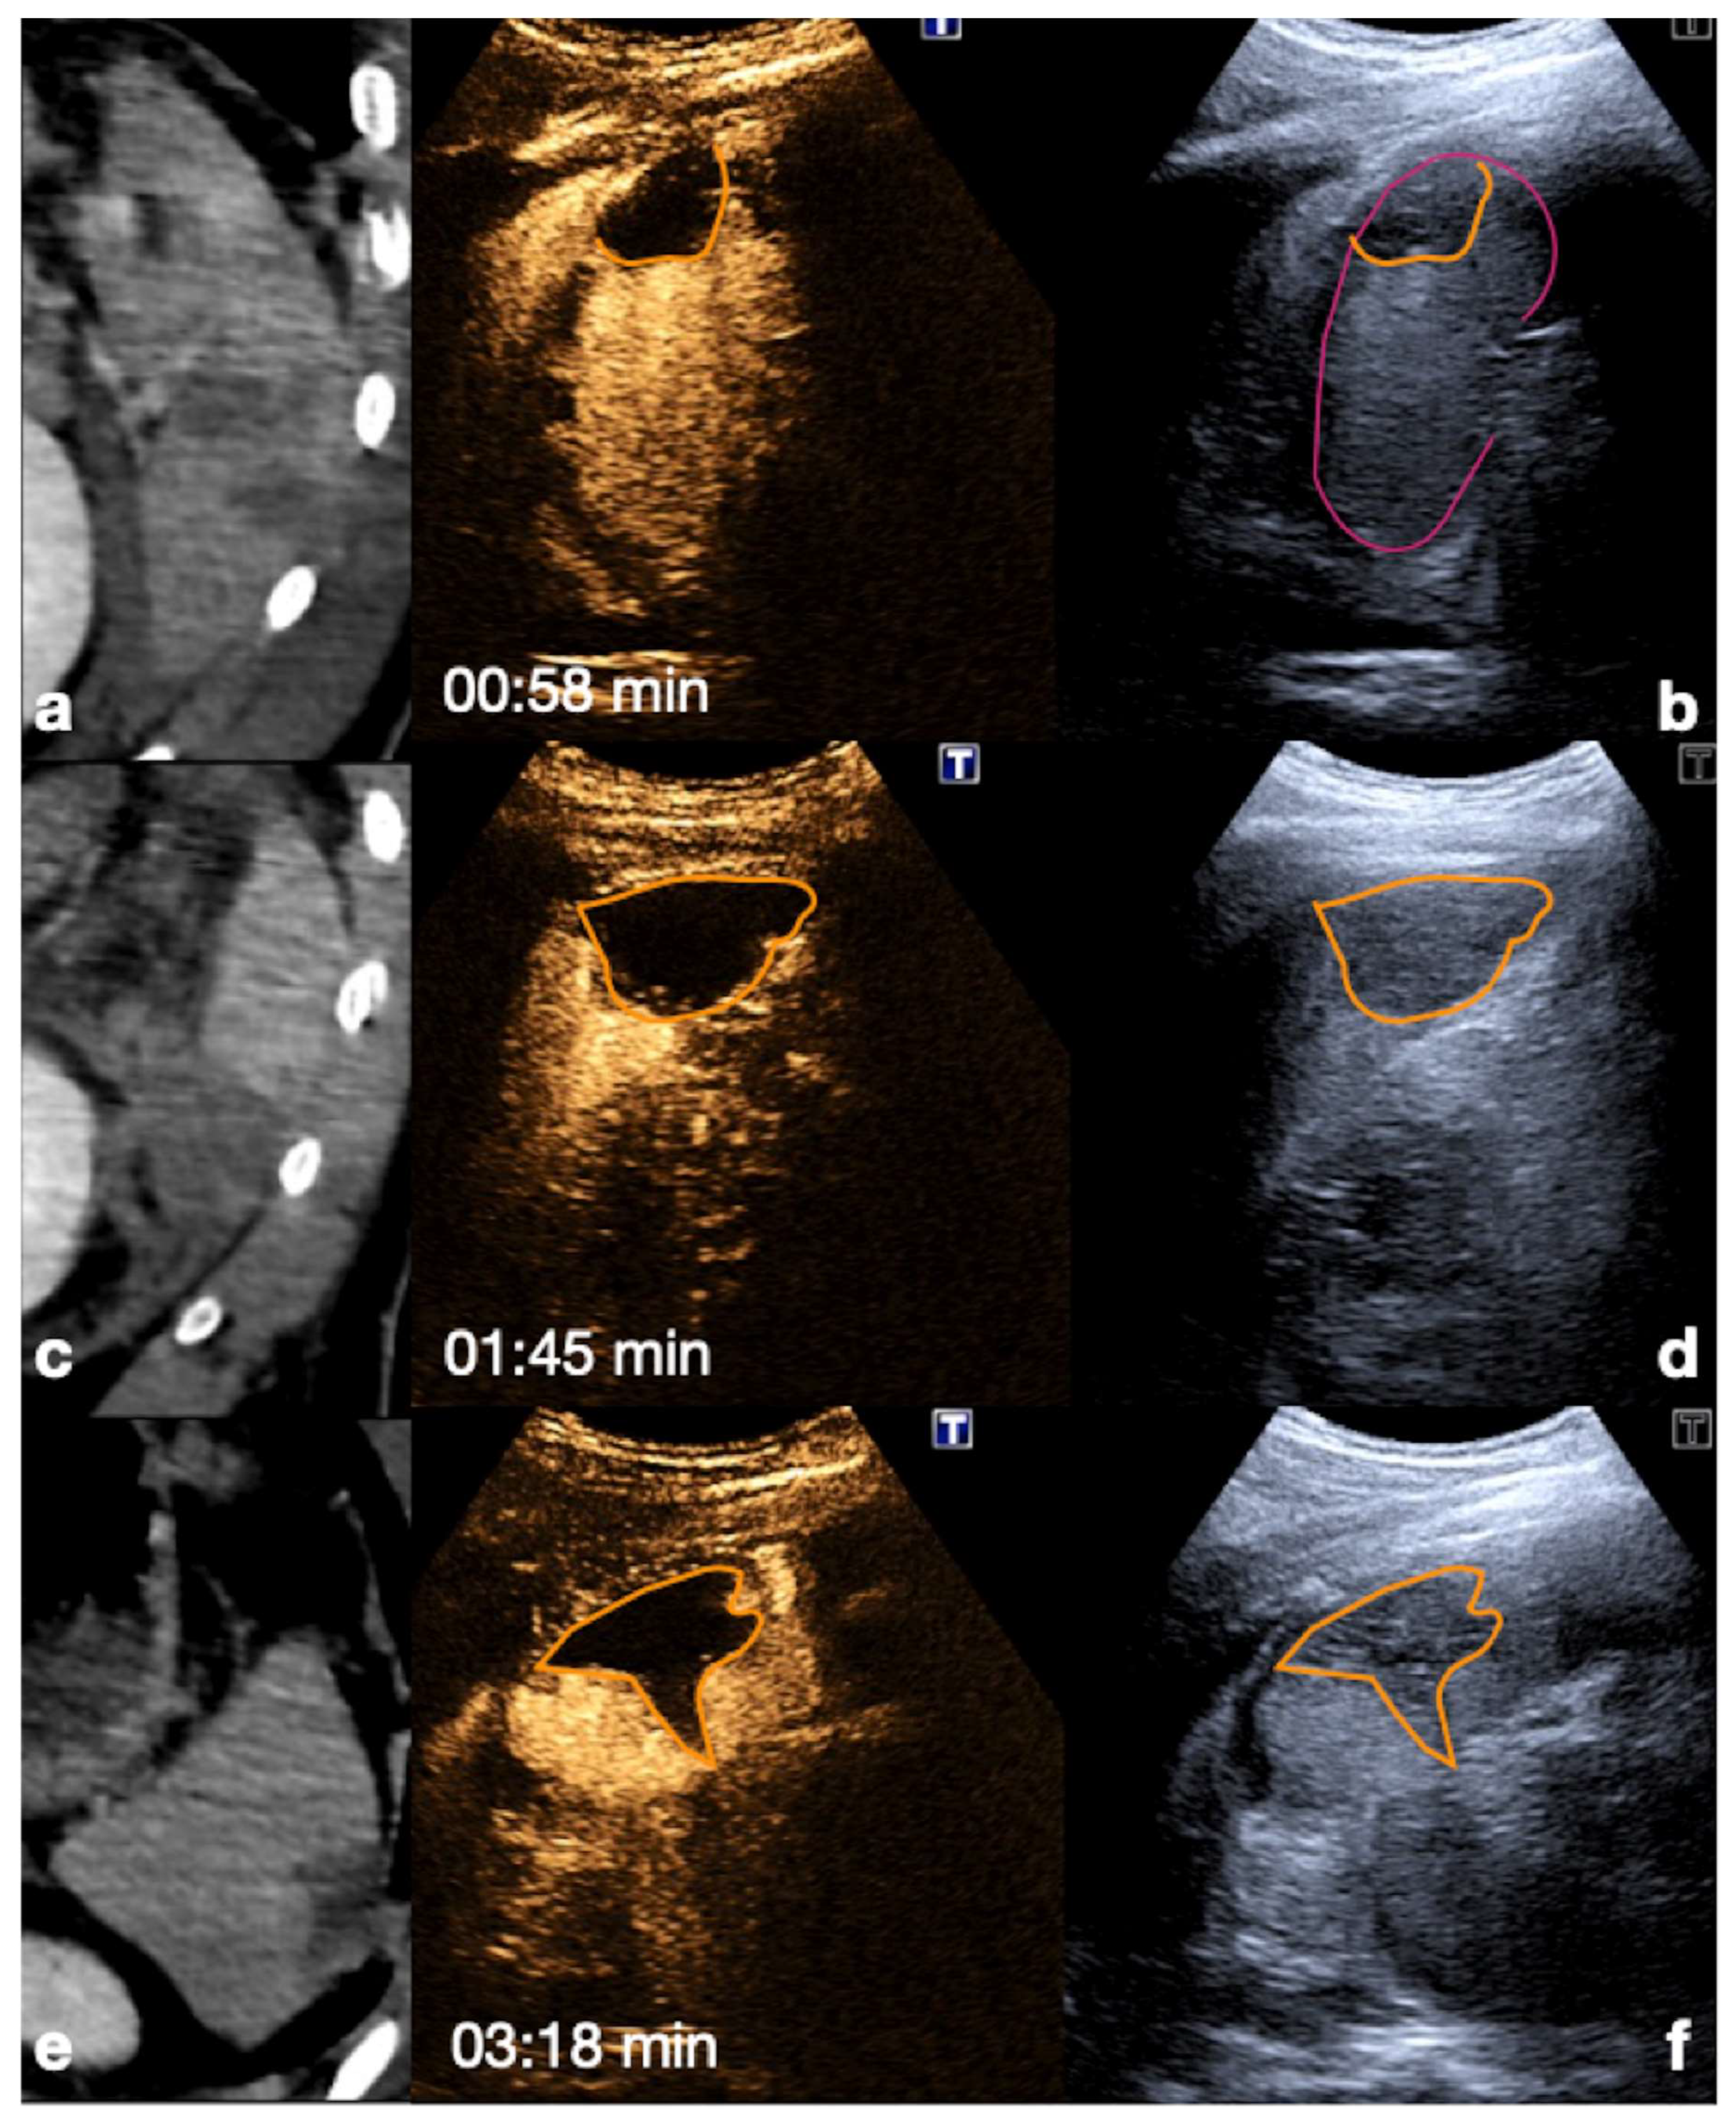

- Parenchymal injuries:

2.3.2. Vascular Injuries

- Active bleeding:

- Contained vascular injuries:

| 10–20 s (early) 20–40 s (late) | Arterial phase: best depiction of contained vascular injuries, such as pseudoaneurysms and arteriovenous fistulas in the early phase. |

| 2–6 min | Venous-late phases: distribution of the contrast in the whole organ. Best time to depict parenchymal injuries. |

| Spleen | Arterial phase: 12–20 s. Venous phase: 40–60 s up to 5–7 min. The best moment to detect organ injury: venous phase. |